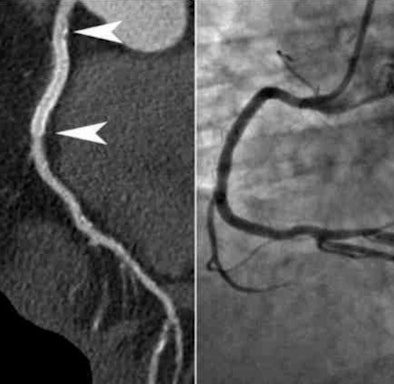

| Coronary CT angiography was performed in high-pitch flash mode after administration of atenolol and glyceryl trinitrate. The heart rate was 57 bpm, and the patient tolerated the procedure well at 100 kV with a total radiation dose of 0.85 mSv. Image courtesy of Dr. Ho Kheng Thye. |

The group from Alvernia Hospital and Tan Tok Seng Hospital in Singapore examined 50 patients (mean age, 55 ± 15 years; 66% male) with coronary stents from an initial cohort of 500 consecutive patients referred for coronary CT angiography over the course of a year.

All patients were scanned in flash mode on a dual-source CT scanner (Somatom Flash, Siemens Healthcare). The mean patient body mass index (BMI) was just 25.3 ± 3.9, and the tube current voltage was based on body weight:

The mean heart rate was 53 beats per minute (bpm) thanks to "aggressive" beta-blocking, he said. Of the group, 18% (n = 9) were scanned at 80 kV, 58% (n = 29) at 100 kV, and 24% (n = 12) at 120 kV following administration of 60 mL contrast and 60 mL saline at 5 mL per second.

Image quality was rated subjectively on a four-point scale depending on the degree of blurring -- with 1 being excellent and 4 nondiagnostic. The stents ranged in diameter from 2.75 to 4.0 mm.

Patients scanned at 80, 100, and 120 kV received doses of 0.38 ± 0.03 mSv, 0.90 ± 0.36 mSv, and 1.78 ± 0.15 mSv, respectively. One patient did not respond to beta-blockage (heart rate, 75 bpm) and was scanned in axial mode receiving a total dose of 2.46 mSv. The remaining 49 patients were scanned in flash mode.